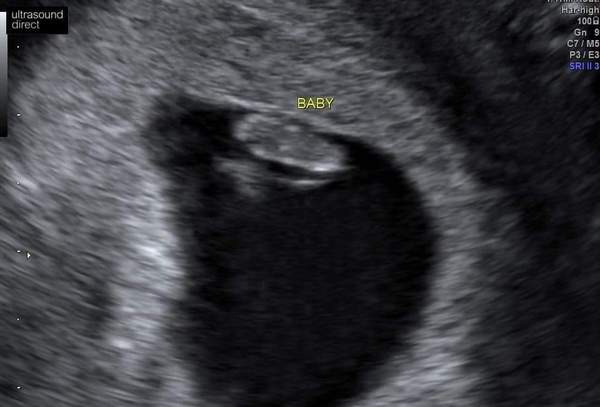

Hey all! Just had my 7 week scan which has dated me as 6+6 which works out for my dates. Everything perfect and healthy. Saw the little heartbeat 💓

@Carysmatic totally worth it for me. I had two scans before from the EPU as well, but the private one was amazing. They explained everything, gave me so much reassurance and it's just amazing seeing the heartbeat so early on 💓

@Islandermum awwww what a cute little bean! So happy all is looking good! Can't wait for mine!

Lovely photo Islandermum! Glad all is as it should be.